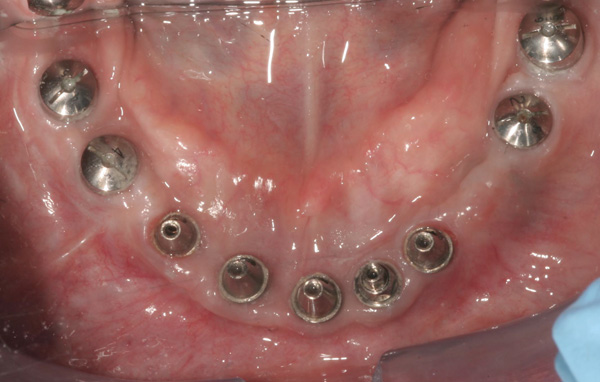

Background: In this case, the patient had a failing mandibular and maxillary dentition due to caries secondary to radiation-induced xerostomia. The patient had had a radical neck dissection to remove a squamous cell carcinoma of the throat 9 years prior to his prosthodontic consultation with the authors. The patient reported a history of radiation therapy following surgery, but did not have a shielding stent. A staged approach was used so as to avoid removable prosthetics on his severely dry soft tissues. He chose to treat his mandibular issues first. Figure 9 shows healing abutments next to the temporarily retained natural teeth, and Figure 10 shows the first-stage custom abutments inserted with relatively good gingival contour and no recession. Recession was clearly seen around all first-stage abutments following adjacent extractions and second-stage implant placement (Figure 11).

Figure 9 Healing abutments.

Figure 9

Figure 10  First-stage custom abutments.

Figure 10